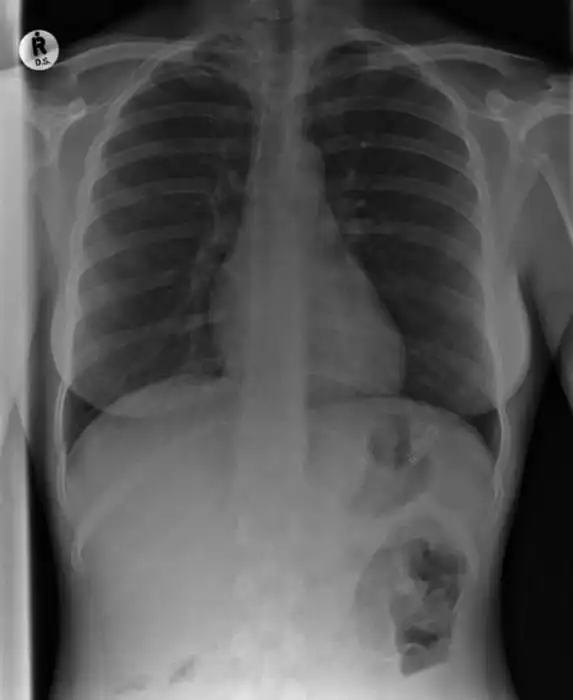

с оторванным пальцем уже не впечатляет, дурных детишек с такими травматическими ампутациями пальцев на работе насмотрелся и назашивался. Часть снимков с фатальными травмами. А с последней не понял. Ну тень средостения, ну загазованная толстая кишка, ничего патологического по костной системе не увидел, только в 10м межреберье слева хрень какая-то сеточкой.